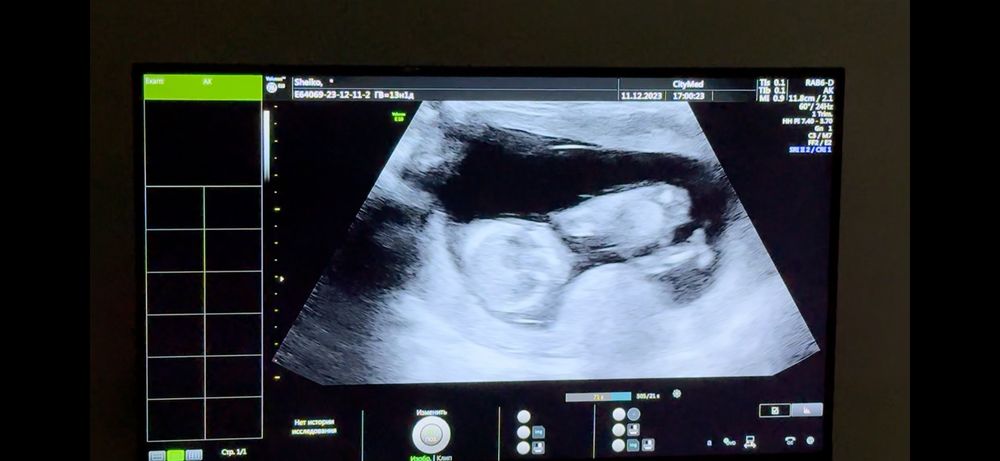

Мальчик или девочка?)

Срок 13+2 по ктр 😁😁😁 Я все узи снимала на видео, вот скриншоты)))

Узист предположил девочку) так ли это?)🥹🥹🥹

у меня вот фото с узи моего сына на сроке 15 недели и там прям сразу понятно что мальчик, а у вас явно девочка))) прикрепляю своё узи мальчика

Девчушка, у вас прям четко видно что девочка, на последней фото где боком лежит и ножки поджаты 🙈 если бы был мальчик что торчал бы писюн хоть чуть чуть, а тут гладко все)